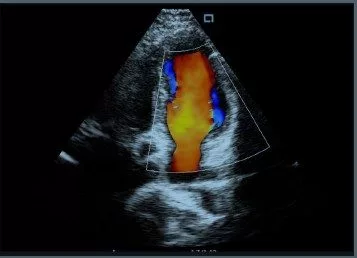

Vascular and cardiology ultrasound examinations requires use of Colour flow Duplex. Ultrasound is a cost effective scanning technique. Scans are performed using High and Low frequency Linear transducers for the real time ultrasound. For Colour Doppler and Pulse wave Doppler Examinations, Linear ultrasound probes are used for the study of the carotid diseases, DVT, possible transient Ischemic attack, assessment of patients with stroke, and conditions of systemic arterial hypertension etc. Transcranial Doppler is a valuable tool for monitoring cerebral blood flow.

Whilst use of Ultrasound for Biopsy procedures, Peri-operative ultrasound guided injections and Neurosurgical procedures are widely used by trained clinicians.

Our portable or mobile ultrasound scanners are designed with image review and recording Includes image archiving facilities post measurements and PACS are easy to use systems for trained and for training purposes for professional sonographers, vascular technologists, echocardiographers, vascular surgeons, physicians, nurses, vascular lab technicians.